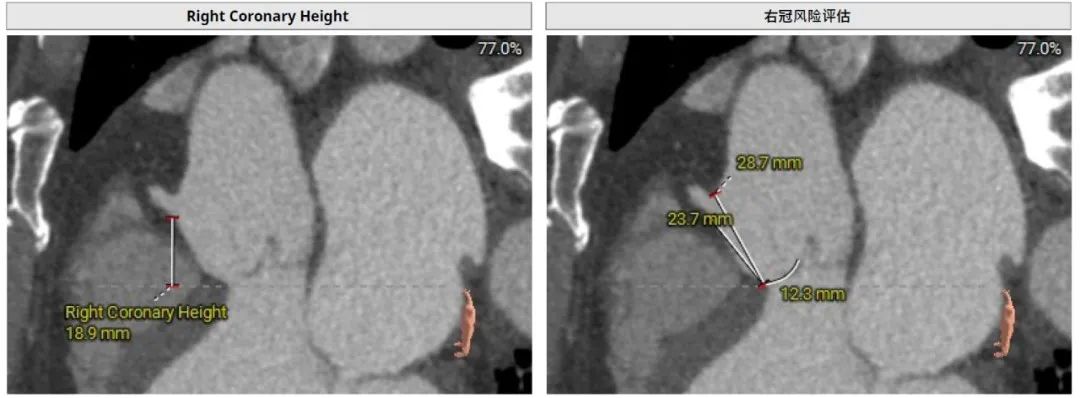

右冠高度:High: 18.9mm

窦宽:Distance L:34.4mm

Distance R:42.2mm

Distance N:40.3mm

STJ:Perimeter: 104.8mm

Mean Diameter:33.4mm

High:36.3mm

左冠高度20.8mm,右冠高度16.4mm,模拟23mm RENATUS瓣膜植入,评估冠脉风险较低。